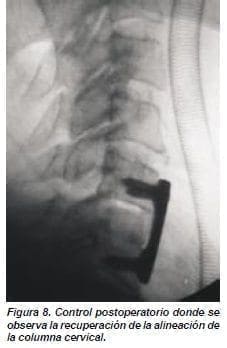

El paciente presentó empeoramiento con aumento del déficit motor en hemicuerpo derecho con parálisis de los músculos dístales en miembro superior derecho. Se decidió realizar tracción cefálica con lo que se redujo un 50% de la luxación en el control a las 12 horas, acompañado de mejoría parcial del dolor y del déficit motor (figuras 5,6). El paciente fue llevado a cirugía donde se le realizó bajo anestesia general y relajación, la reducción completa de la fractura luxación. Se realizó abordaje anterior y se encontró lesión ligamentaria asociada con ruptura del disco intervertebral (figura 7). Se realizó disectomía y artrodesis cervical, injerto de cresta iliaca y una placa #22 entre C5/C6 y se colocó collar cervical permanente (figura 8).

Cuando se reduce la luxación se debe fijar por la alta inestabilidad dada en este tipo de lesiones. Aún hay controversia sobre el tipo de estabilización que se debe realizar.(6,10,13,) La sección de Neurocirugía del HUFSFB, recomienda el abordaje cervical anterior con artrodesis y fijación con placas (figuras 7,8).(3,7,10,11) En algunas ocasiones el sólo abordaje anterior es insuficiente para estabilizar estas luxofracturas por lo cual, en estos casos, se realiza un fijación en 360 grados (anterior y posterior) que puede realizar en el mismo acto quirúrgico.(20) Las complicaciones más frecuentemente asociadas con la cirugía son falla de la fusión, aumento de cifosis o persistencia de cifosis cervical, fístula de líquido cefalorraquídeo e infecciones.(10)